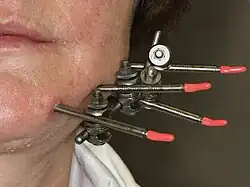

External fixation is a surgical treatment wherein Kirschner pins and wires are inserted and affixed into bone and then exit the body to be attached to an external apparatus composed of rings and threaded rods — the Ilizarov apparatus, the Taylor Spatial Frame, and the Octopod External Fixator — which immobilises the damaged limb to facilitate healing.[1] As an alternative to internal fixation, wherein bone-stabilising mechanical components are surgically emplaced in the body of the patient, external fixation is used to stabilize bone tissues and soft tissues at a distance from the site of the injury.

In this kind of reduction, holes are drilled into uninjured areas of bones around the fracture and special bolts or wires are screwed into the holes. Outside the body, a rod or a curved piece of metal with special ball-and-socket joints joins the bolts to make a rigid support. The fracture can be set in the proper anatomical configuration by adjusting the ball-and-socket joints. Since the bolts pierce the skin, proper cleaning to prevent infection at the site of surgery must be performed.

The parts of an external fixator include:

- Schanz pin

- Connecting rods

- Clamps

3. Pin-track infection - This is less likely with good operative technique. Nevertheless, meticulous pinsite care is essential to avoid infection. [2]